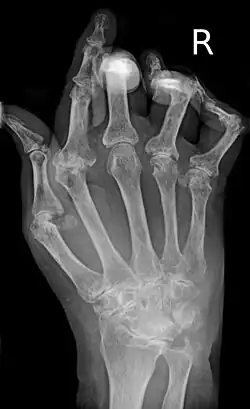

- Bildgebende Verfahren: Zu Beginn und im Verlauf sind Röntgen- oder MRT-Untersuchungen erforderlich, um Schädigungen der Knochen (Erosionen) abschätzen zu können. Typische radiologische Befunde, vor allem im Bereich der Hände, sind gelenknahe Entkalkungen, subchondrale (bzw. gelenknahe[12]) Osteoporose, Destruktionen des umliegenden Knochens, Ankylosen und Gelenkfehlstellungen (Knopflochdeformität, Schwanenhalsdeformität, Ulnardeviation).

Der Krankheitsbeginn ist oft schleichend, kann aber auch plötzlich eintreten, mit Schmerzen in den kleinen Finger- oder Zehengelenken. Es können auch andere Gelenke betroffen sein, insbesondere Hand-, Knie-, Schulter, Fuß-, Hüftgelenke. Typischerweise werden bevorzugt die Handwurzelknochen, die Fingergrundgelenke (Metacarpophalangealgelenke) und die Fingermittelgelenke (proximale Interphalangealgelenke, PIP) befallen. Die Fingerend- und Zehenendgelenke (distale Interphalangealgelenke, DIP) sind im Gegensatz zur Psoriasisarthritis nicht betroffen. Die betroffenen Gelenke schwellen an und sind überwärmt. Eine Rötung der betroffenen Gelenke kann hinzukommen. Eine symmetrische (= beidseits auftretende) Synovitis der stammfernen Gelenke ist typisch, aber nicht zwingend. Morgens sind diese Symptome zumeist am stärksten ausgeprägt; es handelt sich dabei um die symptomatische Morgensteife. Im Krankheitsverlauf werden immer mehr Gelenke befallen. Unbehandelt führt sie häufig zur Gelenkzerstörung.